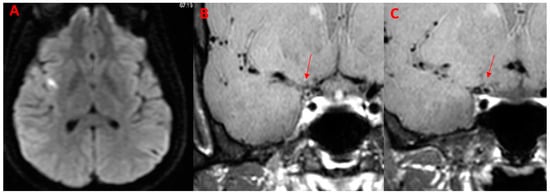

7. Legend

| 50Y, F | 1 | Present | Present | Parietal lobe | MCA (M1) | None | Present | Supratentorial, subtentorial |

| 52Y, F | 1 | Present | Present | Multiple subcortical in MCA territories | MCA M2 | None | Absent | // |

| 53Y, M | 1 | Present | Present | Fight corona radiata | ICA | ACOP | Present | Supratentorial |

| 63Y, M | 1 | Present | Present | Multiple Subcortical in ACA, MCA Territories and Pons | ACA (A2) | None | Present | Supratentorial, subtentorial |

| 29Y, F | // | Absent | Absent | No | ICA | ACA (A1), MCA (M1) | Absent | // |

| 32, M | // | Absent | Present | No | ICA | ACA (A1), MCA (M1) | Absent | // |

| PCNSV (n = 6) | 4 (66.7%) | 3 (50.0%) | 0 (0.0%) | 2 (33.33%) | 5 (83.3%) | 3 (50.0%) | 5 (83.3%) multiple: 2 (40.0%) | 4 (66.7%) | 0 (%) | 5 (83.3%) | 1 (16.7%) | MCA (M1, M2), ACA (A1, A2), ICA, ACOP |